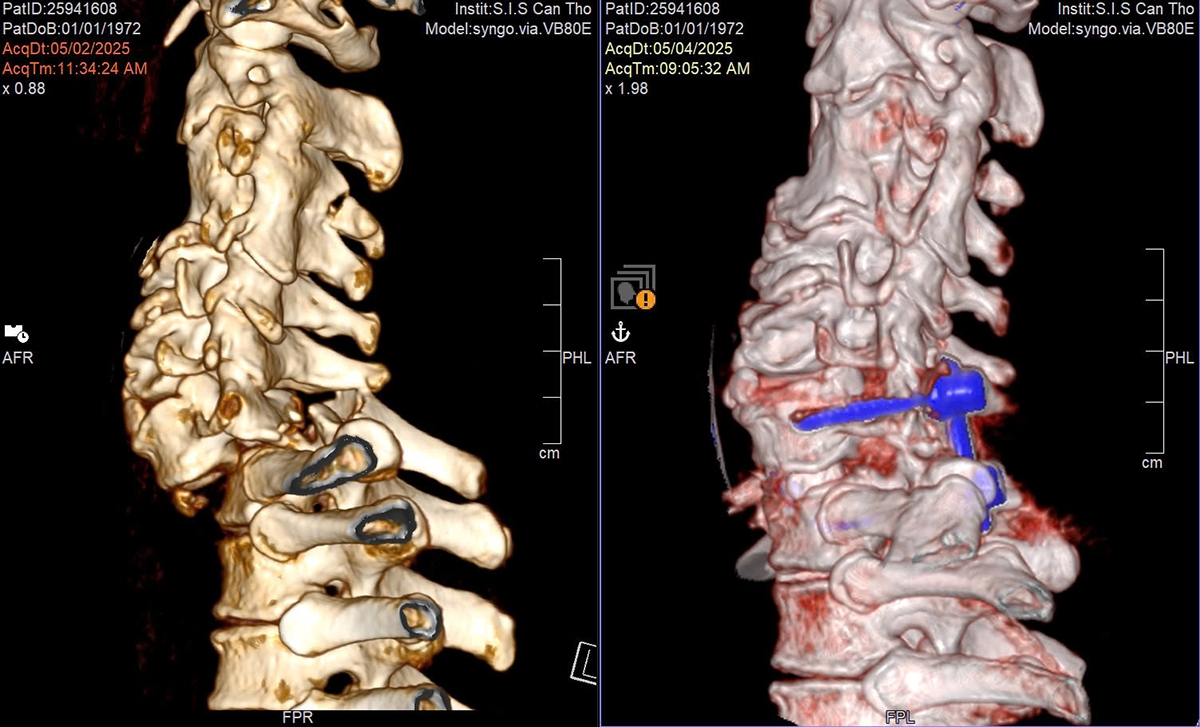

Tại đây, kết quả CT cho thấy ông T. bị gãy trật nặng cột sống cổ đoạn C7–T1, thân đốt sống cổ C7 lệch hoàn toàn ra trước kèm theo trật cài mặt khớp 2 bên.

Ngày 4/5, chụp cộng hưởng từ (MRI) cột sống cổ để đánh giá mức độ và các nguyên nhân khác gây chèn ép tủy thì phát hiện chèn ép tủy sống di lệch đốt sống đơn thuần từ phía trước, không kèm theo theo tụ máu hay mảnh vỡ của xương hoặc đĩa đệm.

Chụp cộng hưởng từ (MRI) cột sống cổ để đánh giá mức độ và các nguyên nhân khác gây chèn ép tủy bệnh nhân

Trong 9 tiếng, ekip cho bệnh nhân nằm sấp, phần đầu được cố định chắc chắn để phẫu thuật từ phía sau giải phóng tủy sống bị chèn ép, nắn chỉnh và cố định lại đốt sống bằng vít; người bệnh được theo dõi liên tục và kiểm tra trên màn hình tăng sáng để đảm bảo dụng cụ đúng vị trí và hiệu quả; sau đó kết hợp ghép xương tự thân và nhân tạo để tăng cường giữ vững cột sống và sự liền xương về lâu dài.

Tiếp theo, bệnh nhân được đổi tư thế sang nằm ngửa để tiếp tục xử lý phần gãy ở phía trước cổ: loại bỏ phần đĩa đệm tổn thương, kiểm tra các mảnh vỡ nhỏ của đĩa đệm và xương vỡ không thể nhìn thấy trên MRI/ CT bằng kính vi phẫu nhằm giải ép rễ thần kinh tốt nhất có thể và cuối cùng đặt mảnh ghép chịu lực có ghép xương nhân tạo giữa 2 đốt sống nhằm khôi phục lại đường cong sinh lý cột sống cổ.